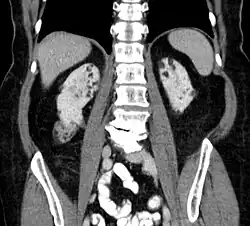

Kidneys

Between 26% and 80% of TSC patients have benign tumors of the kidneys called angiomyolipomas, with hematuria being the most frequent presenting symptom.[8] TSC angiomyolipomas differ from non-TSC angiomyolipomas in age of presentation (31.5 years vs 53.6 years), mean tumor size (8.2 cm vs 4.5 cm), and percentage of cases requiring surgical intervention (50% vs 28%).[8] Although benign, an angiomyolipoma larger than 4 cm is at risk for a potentially catastrophic hemorrhage, either spontaneously or with minimal trauma.